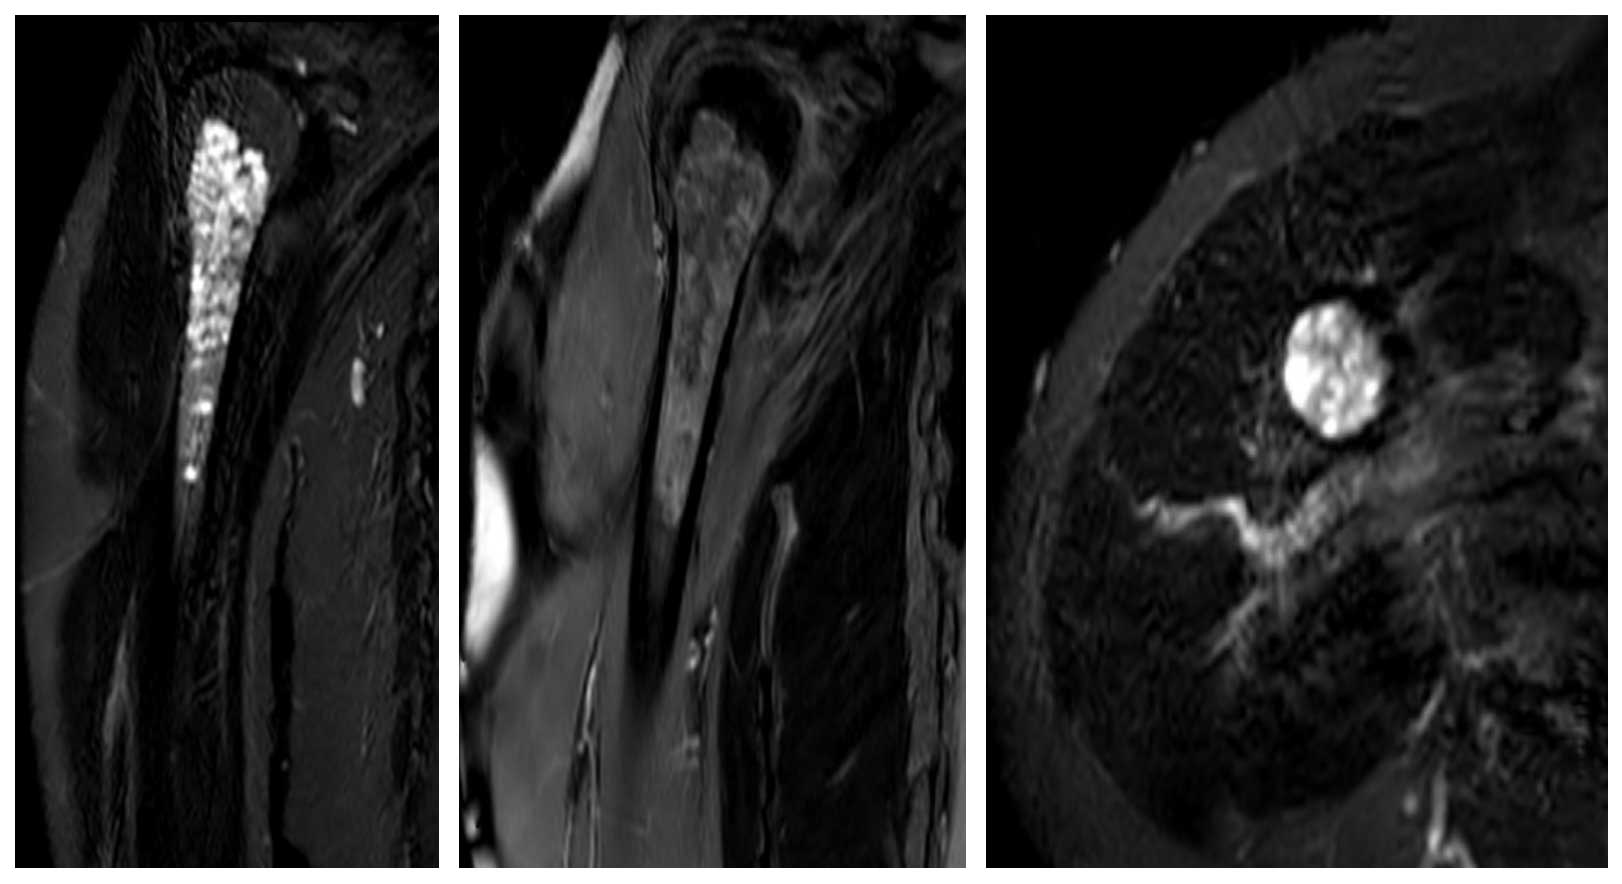

Ameliyat Öncesi: MR’da uzun segment boyunca kemiğin içini dolduran heterojen kıkırdak tümörü görülmekte.